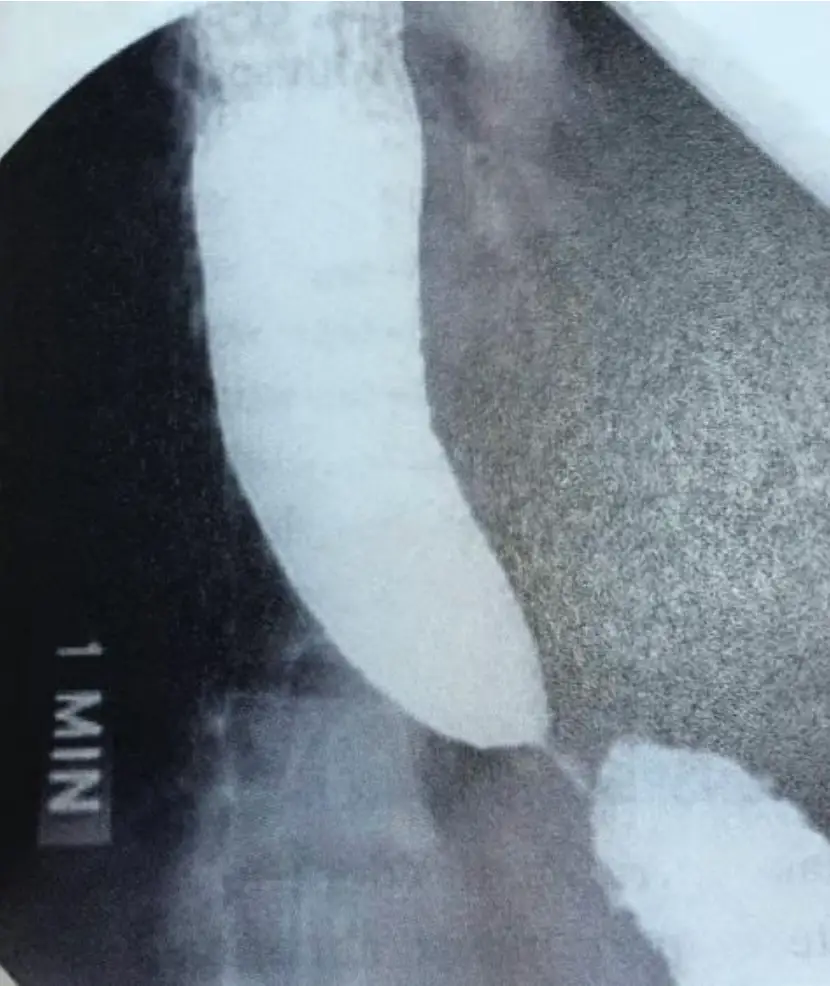

25歲男性病人因吞嚥困難、胸痛及體重減輕接受胃鏡檢查,結果為正常。個案進一步接受上消化道攝影結果如圖,下列何者為正確診斷?

本題上消化道攝影(barium swallow / upper GI series)顯示:食道下段(遠端)呈現典型的鳥嘴狀狹窄(bird's beak sign),鋇劑在食道胃接合處(esophagogastric junction, EGJ)呈現對稱性、平滑、逐漸收縮的錐形狹窄,形如鳥嘴,鋇劑通過受阻。食道近段(體部)可見擴張,內含積存的鋇劑與分泌物。影像標記「1 MIN」提示這是吞鋇後第 1 分鐘仍見滯留的影像,反映食道排空延遲(esophageal emptying delay)。整體影像所見高度符合**食道弛緩不能(achalasia)**的典型放射線學表現,與食道廣泛性痙攣(diffuse esophageal spasm, DES)的「螺旋狀」或「串珠狀」影像不同,亦與食道癌的不規則、非對稱性狹窄不同。